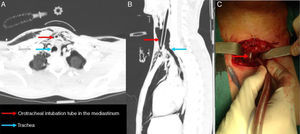

We report the case of a 17-year-old male patient with closed cervical spine injury due to a traffic accident, hemodynamically stable, with continuous desaturations requiring orotracheal intubation. Computed tomography performed in our hospital revealed complete cervical tracheal disruption with a 5cm proximal to distal dehiscence, with the orotracheal tube located in the mediastinum (Fig. 1A and B). Given these findings, emergency surgery was performed, with anterior transverse cervicotomy and intrafield intubation (Fig. 1C), and end-to-end tracheal anastomosis with unloading distal tracheotomy. The patient was extubated on the third day after surgery, and discharged 9 days after the intervention, with withdrawal of the tracheotomy tube and closure after confirmation of airway patency and adequate gastrointestinal ingestion. Six months later, dysphonia persisted due to paralysis of both vocal cords in the paramedian position.